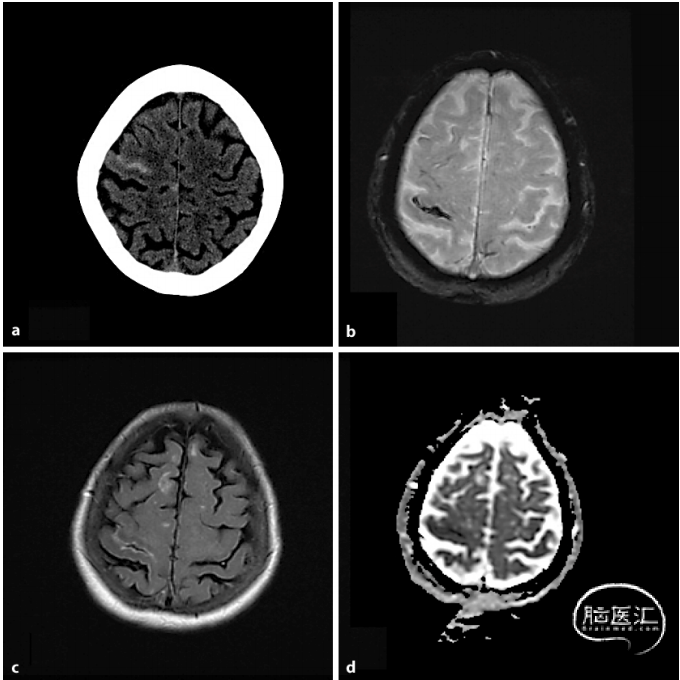

上图为患者发病当天的CT

可以看到左侧顶叶的沟里有高信号,很容易让人认为是蛛网膜下腔出血,或者是其他考虑。患者一天后做了FLAR,如下图所示:

显示也是一个高信号,我这里没有贴T1,T1是等信号。同时做了一个MRA,发现了左侧大脑中动脉的一个狭窄。

7天后的CT显示,高密度已经消失,如下图所示:

我们为患者行球囊扩张手术,因为患者身体放了起搏器,不能做核磁,所以脑组织用CT去复查,可以看出这个患者治疗后的预后还是不错的,即使他有蛛网膜下腔出血。如下图所示:

术后脑影像

🔽